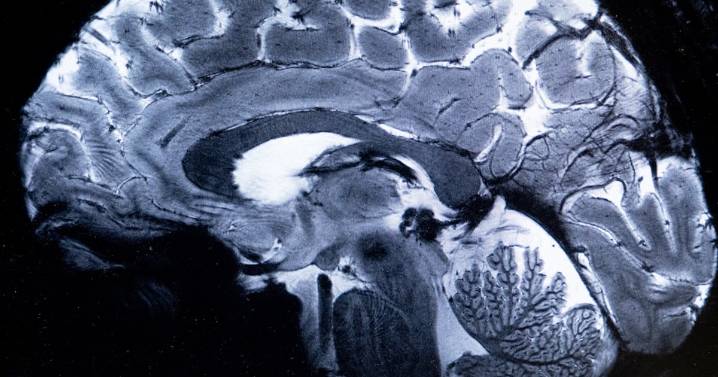

A new study has found that adolescence doesn’t just last through our teens and early twenties, but in fact continues into our early thirties. Researchers at the University of Cambridge studied the brain scans of 4,000 people and discovered the brain goes through five distinct phases in life: childhood from birth to age 9, adolescence from age 9 to 32, adulthood from age 32 to 66, early aging from 66 to 83, and late aging from 83 onwards. During the adolescent phase, the brain’s connections undergo the biggest shift, becoming far more efficient but also more susceptible to the onset of mental health disorders. The brain then “peaks” at about age 32 and enters a period of stability—adulthood—that represents its longest era. During adulthood, intelligence and personality plateau, until connec

Brain Study Reveals Adolescence Lasts Until Shockingly Late in Life